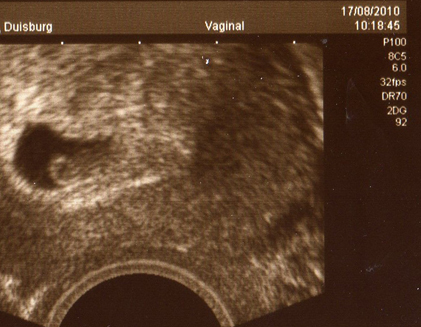

Mach dir mal keine Gedanken wegen des zurückdatieren! Ich wurde beim FA auch zurückdatiert auf 6+3 obwohl ich laut GE bei 7+0 war!

Das kommt immer drauf an wie sich die Krümel entwickeln!

Als ich dann bei der ersten VU war beim FA war der Krümel ordentlich gewachsen und dann auch zeitgerecht! Mein FA hat z.B. gar nicht den ET von GE genommen sondern ganz normal ausgerechnet und das auch so in den MuPa eingetragen und bis jetzt hat sich die Kleine immer zeitgerecht entwickelt!